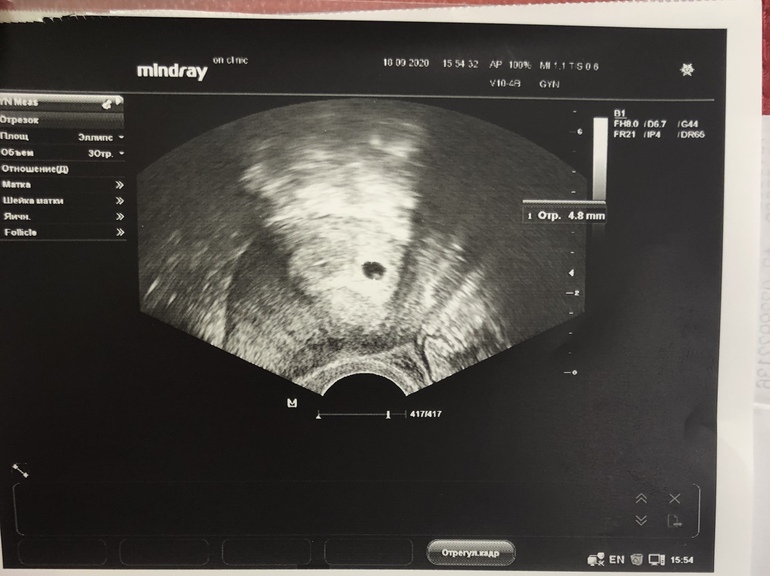

Первое узи!

Я БЕРЕМЕННА !Сегодня 16дпп, пригласили на приём. Увидела свою крошку 😍. По сроку 3-4 недели

Теперь 26 числа пойду слушать сердечко!